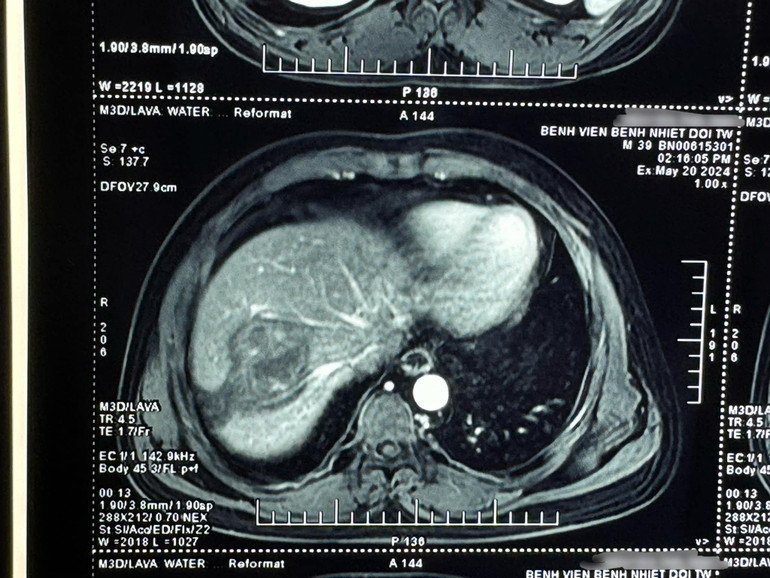

Tiến sĩ Vũ Minh Điền, Phó Trưởng khoa Nội Tổng hợp, Bệnh viện Bệnh Nhiệt đới Trung ương cho biết, qua thăm khám lâm sàng và khai thác tiền sử của bệnh nhân, các bác sĩ đã nghĩ đến bệnh cảnh sán lá gan lớn khi các xét nghiệm ban đầu cho thấy có bạch cầu ái toan tăng cao và hình ảnh chụp phim cộng hưởng từ gan hướng nhiều đến bệnh sán lá gan lớn.

| Hình ảnh ổ sán lá gan lớn của bệnh nhân. |